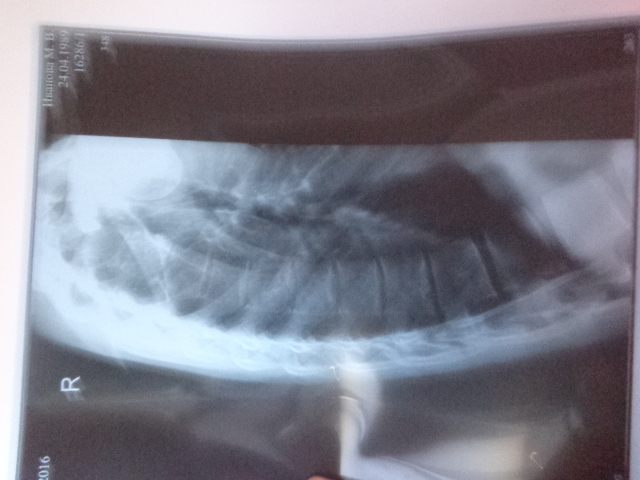

мне 27 лет.кифосколиоз шейермана-мау со школы.в последнее время ситуация ухудшилась-кифоз прогрессирует.нужна ли мне операция?какая у меня степень кифоза?помогите определить!мне стало тяжелее дышать и стали чувствоваться перебои в работе сердца,постоянно шаткость и головокружения-по анализам сказали что ничего катастрофического.но жить стало тяжелее,постоянно болит спина,делаю лфк.

DSC03252.JPG

DSC03251.JPG

DSC03837.JPG